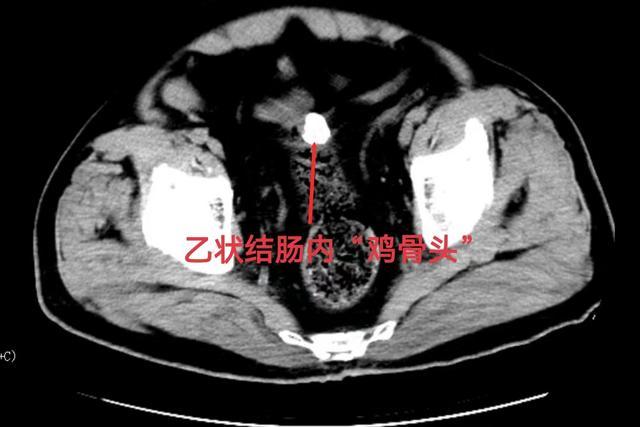

术后复查CT发现:下腹部乙状结肠内有一处约3x3cm的高密度影,考虑患者病程长达10天,食道局部穿孔、窦道变大,“鸡骨头”应该是经扩大的食管溃疡口掉落胃肠道,将经肠道排出体外。